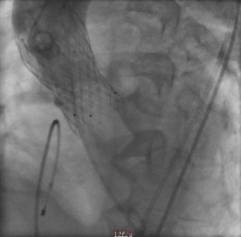

经过周密的筹备,3月5日上午,何贵新主任团队在广东省心血管病研究所罗建方教授团队的指导下,“临时起搏器植入、鞘管植入、跨瓣、球囊扩张、精准定位、瓣膜释放.......”,历经1小时余,顺利为韦奶奶行经导管主动脉瓣置换术(TAVR),置入新的主动脉瓣,打开心脏血液流出的第一道门,手术创口仅针眼大小。术后,复查超声心动图提示人工主动脉瓣膜工作良好,心脏血液泵出顺畅,术前跨瓣压差62 mmHg术后降至差2mmHg,手术非常成功,术后第2天即可下床活动。

另外一例患者谢爷爷面对一场惊心动魄的“生死战”。首先,在球囊抵达主动脉瓣口,刚准备扩开为瓣膜植入创造条件时,瞬间出现室颤,心跳骤停。“快,除颤、心肺复苏!”团队医护人员迅速抢救,同时另一组人将瓣膜送入心脏,跨瓣压差由术前127mmHg降至术后3mmHg。术后送入ICU治疗,第3天,谢爷爷病情稳定,即可下床活动。